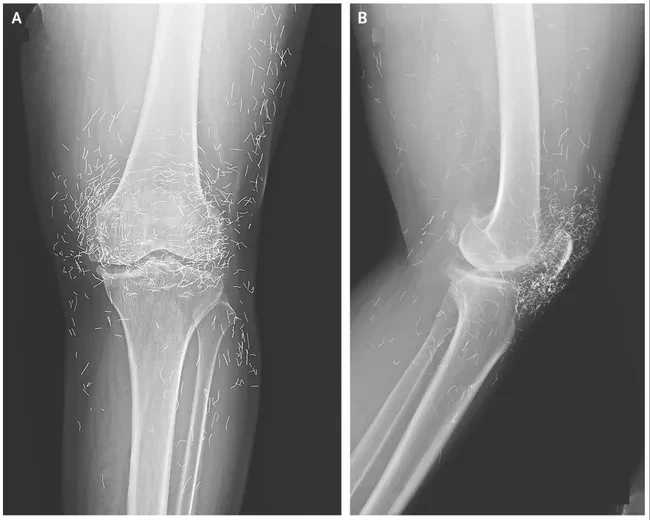

Okozott némi dilemmát az eset, de a szálakat végül nem távolították el.